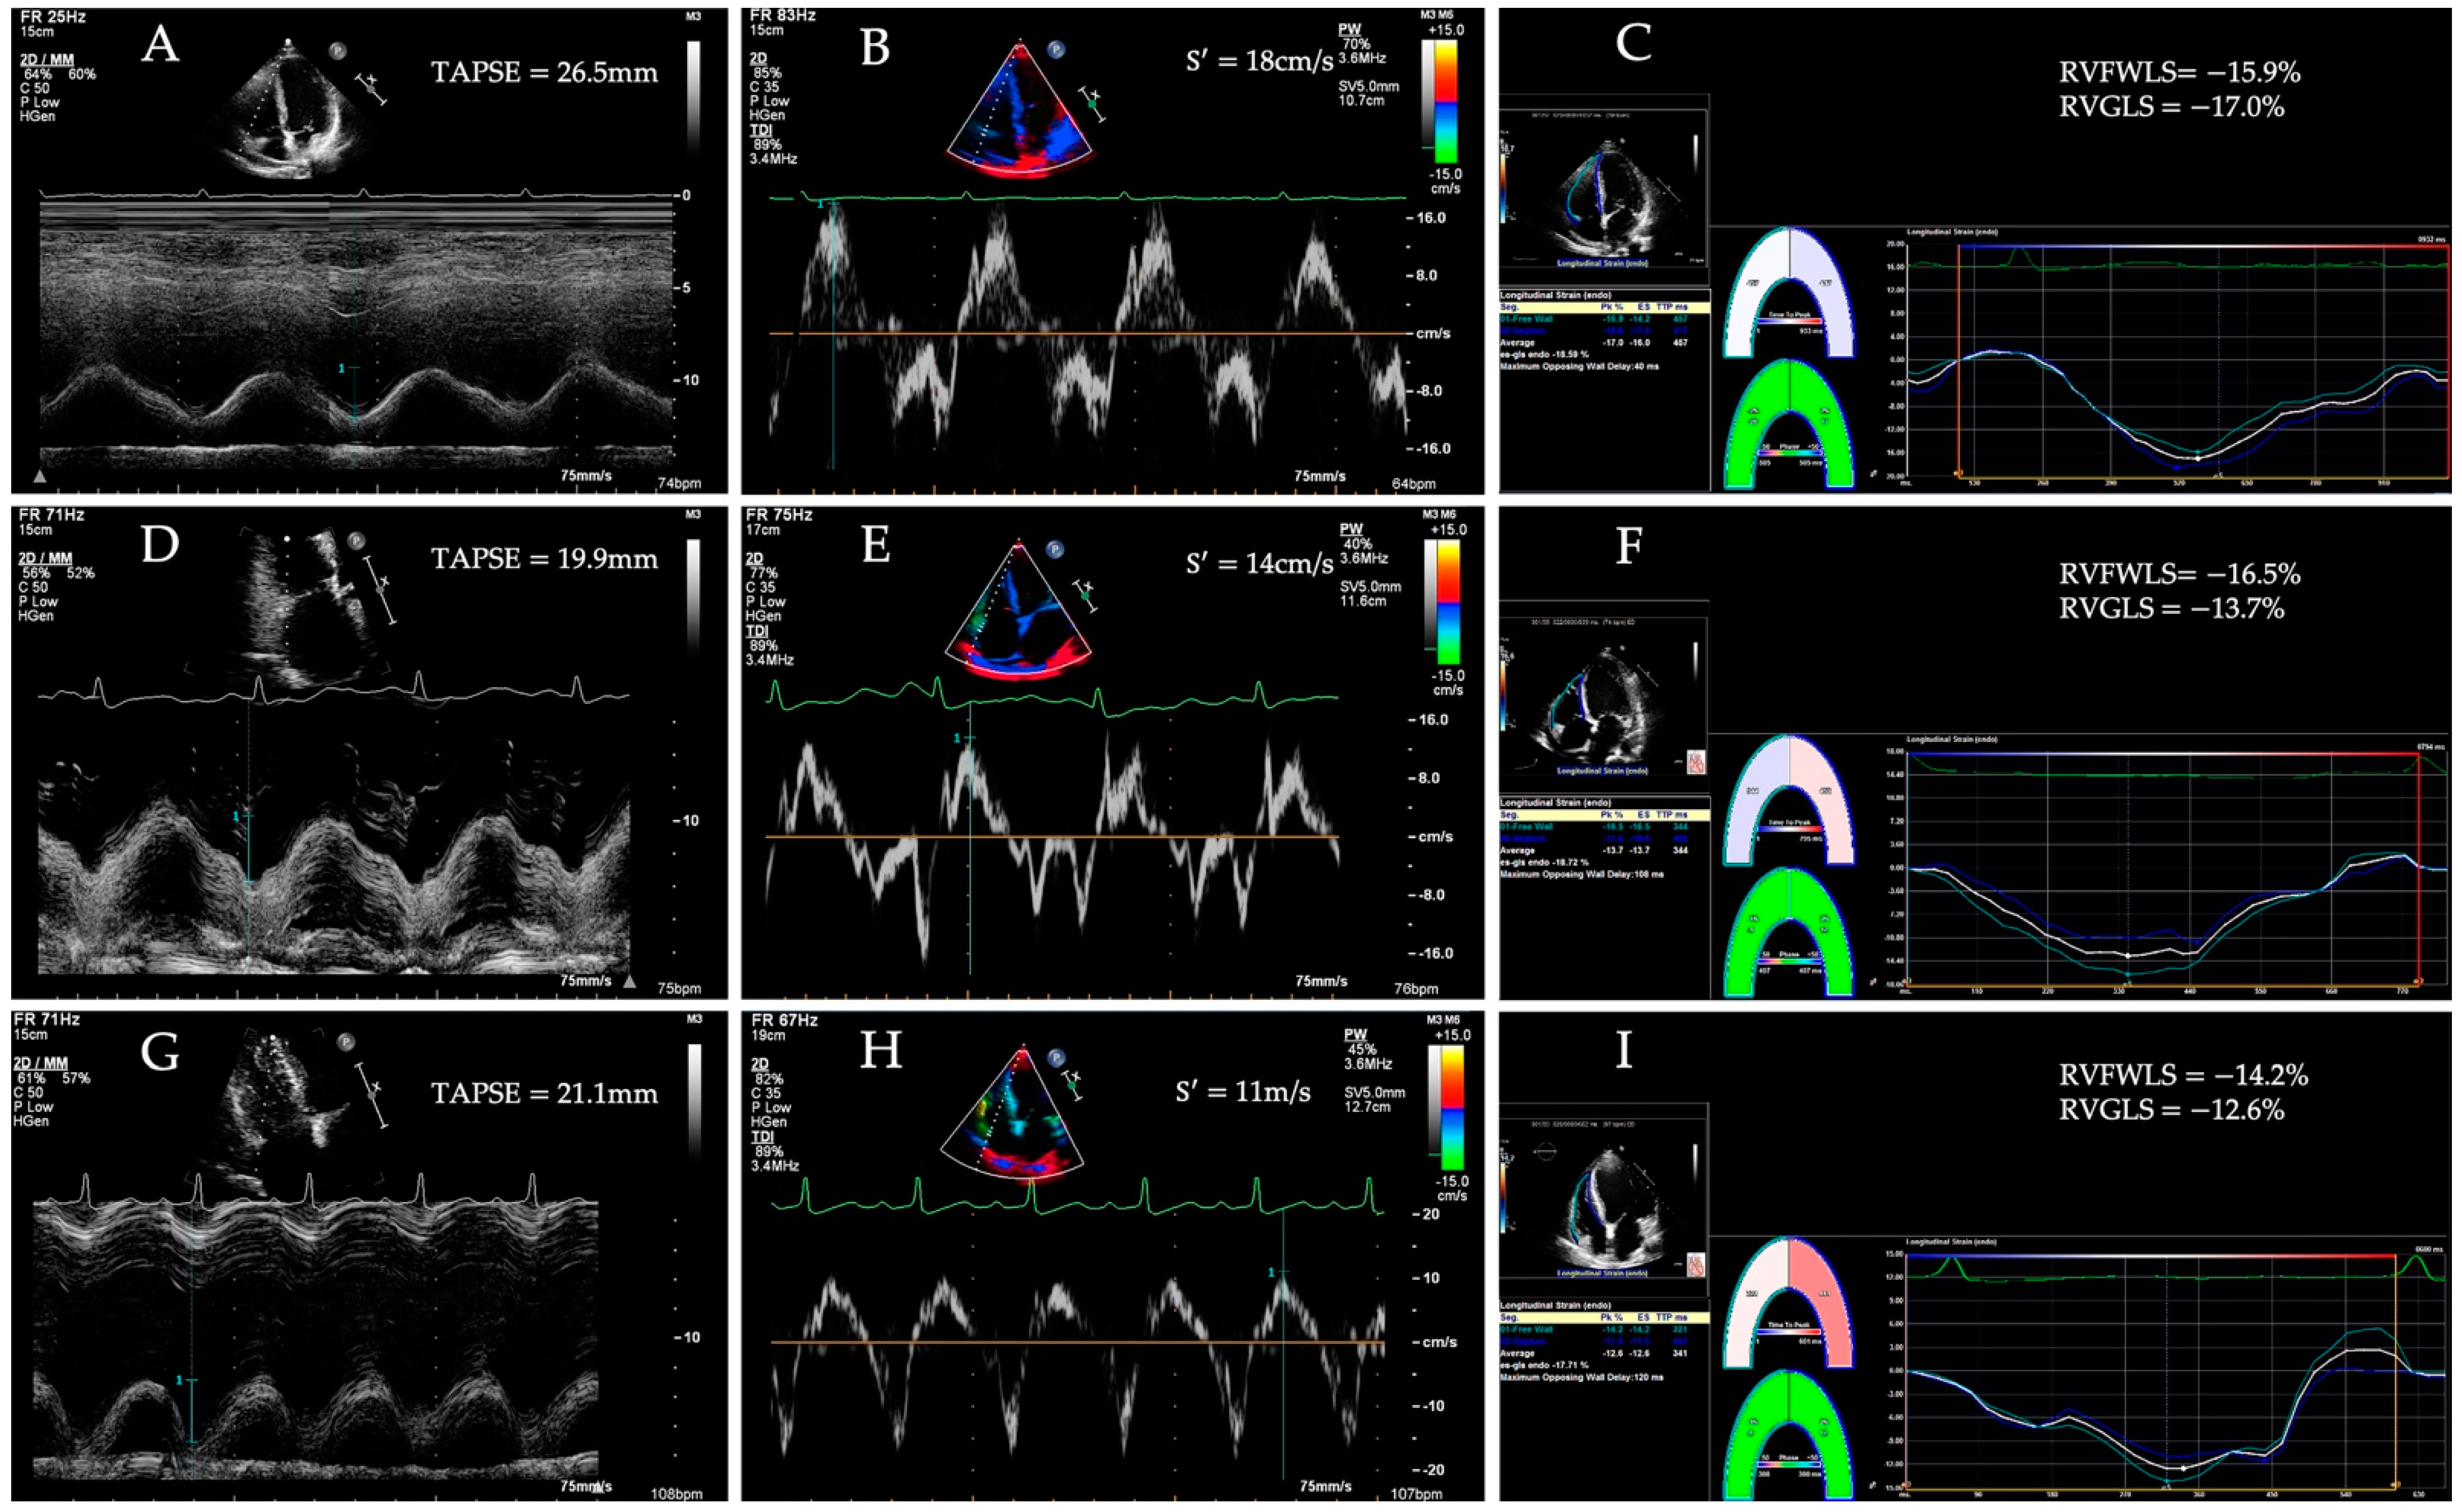

In recent years, two-dimensional speckle tracking echocardiography (2D-STE) has been developed as a new imaging tool of evaluating cardiac function. 2D-STE is the two-dimensional tracking of unique speckle patterns created by the constructive and destructive interference of ultrasound beams within myocardial tissue [46]. 2D-STE allows a precise quantification of RV strain and an early detection of the subclinical RV dysfunction, providing comprehensive diagnostic and prognostic information in patients with a variety of cardiovascular diseases [16,47,48,49,50,51,52,53,54]. RVLS is measured in the RV-focused apical four-chamber view, which provides better visualization of the whole right ventricle, and avoids foreshortening of the RV apex [22]. The frame rate is between 60 and 80 frames per second. The high-quality images are essential for RV strain analysis [55]. After endocardial border delineation, the software automatically segments the right ventricle into six segments (basal, middle, and apical segments of both the RV free wall and the interventricular septum), and tracks the movement of speckles in the myocardium throughout the cardiac cycle on two-dimensional echocardiographic images [56]. Finally, RV longitudinal strain curves of free wall and septum are automatically generated by the software (Figure 1). The average value of longitudinal strain of the basal, middle, and apical segments of the RV free wall is longitudinal strain of the RV free wall (RVFWLS), whereas RV global longitudinal strain (RVGLS) represents the average value of RV six segments [57,58,59]. RVGLS may be affected by LV systolic function owing to the fact that the interventricular septum is conventionally regarded as one part of the left ventricle. Therefore, the published guideline of the ASE and the European Association of Cardiovascular Imaging (EACVI) recommend a normal value only for RVFWLS [60].

Figure 1. Longitudinal strain of the RV free wall and septum using two-dimensional speckle tracking echocardiography.

7. RV Longitudinal Strain in HF Patients with Preserved Traditional RV Function Parameters

Several studies have reported the predictive value of RV longitudinal strain in HF patients with preserved conventional RV systolic function parameters, such as TAPSE and S′. However, these traditional RV function indicators could not accurately assess and represent global RV systolic performance because they only reflected segmental function of the right ventricle [35,88]. RVLS, as a new echocardiographic parameter, overcomes the limitation of angle dependency of TAPSE and S′, and it has incremental clinical value in detecting subclinical RV dysfunction. The current findings regarding RV longitudinal strain in patients with preserved traditional RV function parameters are depicted in Table 3. Morris et al. [89] compared 218 patients with HFpEF and 208 patients with HFrEF with controls and measured RVGLS and RVFWLS by 2D-STE. They found that the normal range of RV systolic strain in the normal population was as follows: 2D-RVGLS −24.5 ± 3.8% and 2D-RVFWLS −28.5 ± 4.8%. They demonstrated that the conventional echocardiographic parameters such as TAPSE, S’, RVFAC in patients with HFpEF or HFrEF were within the normal range, but both 2D-RVGLS and 2D-RVFWLS decreased. Their findings indicated that 2D-RVGLS and 2D-RVFWLS were related to the clinical status of patients with HF. More importantly, subtle RV longitudinal systolic dysfunction can be detected by both 2D-RVGLS and 2D-RVFWLS in a considerable proportion of patients with HFrEF and a smaller group of patients with HFpEF despite preserved TAPSE, RVFAC and S’. Carluccio et al. [24] demonstrated that 2D-RVFWLS is impaired in patients with HFrEF with preserved TAPSE. According to the lasso-penalized Cox-hazard model, impaired 2D-RVFWLS was an independent predictor of death and HF rehospitalization, providing incremental prognostic value over TAPSE and other recognized clinical and echocardiographic predictors of end points and improving risk stratification. The best cutoff value of 2D-RVFWS for prediction of outcome was −15.3%. The results of this study also demonstrated the potential of RVLS in detecting subtle RV systolic dysfunction. Three case examples of altered RV strain despite preserved TAPSE and S-TDI in patients with HFpEF, HFmrEF and HFrEF are shown in Figure 3.

Figure 3. Tricuspid annular plane systolic excursion (TAPSE), systolic velocity of the tricuspid annulus (S’), longitudinal strain of the RV free wall and RV global longitudinal strain in patients with HFpEF (AC), HFmrEF (DF) and HFrEF (GI).